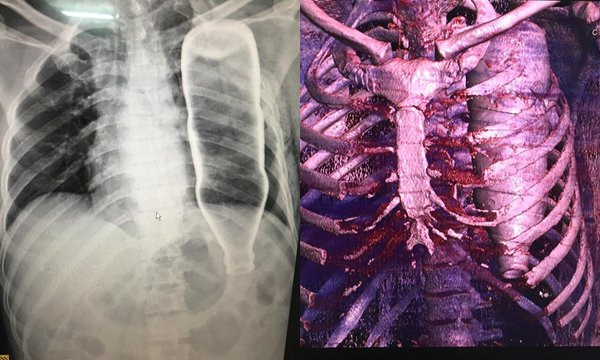

Chai thủy tinh nằm trong lồng ngực

Ngày 28/5, Bệnh viện Đà Nẵng tiếp nhận bệnh nhân N.H.B (53 tuổi, Quảng Nam), theo lời người nhà, trong lúc vấp ngã, ông B. bị một vật chui vào nhưng không rõ vật gì. Sau khi tiến hành chụp X-quang và CT phát hiện chai đựng nước thuỷ tinh nằm trọn trong lồng ngực bệnh nhân, chai nước này làm bệnh nhân bị gãy 2 xương sườn, lõm xương đòn.